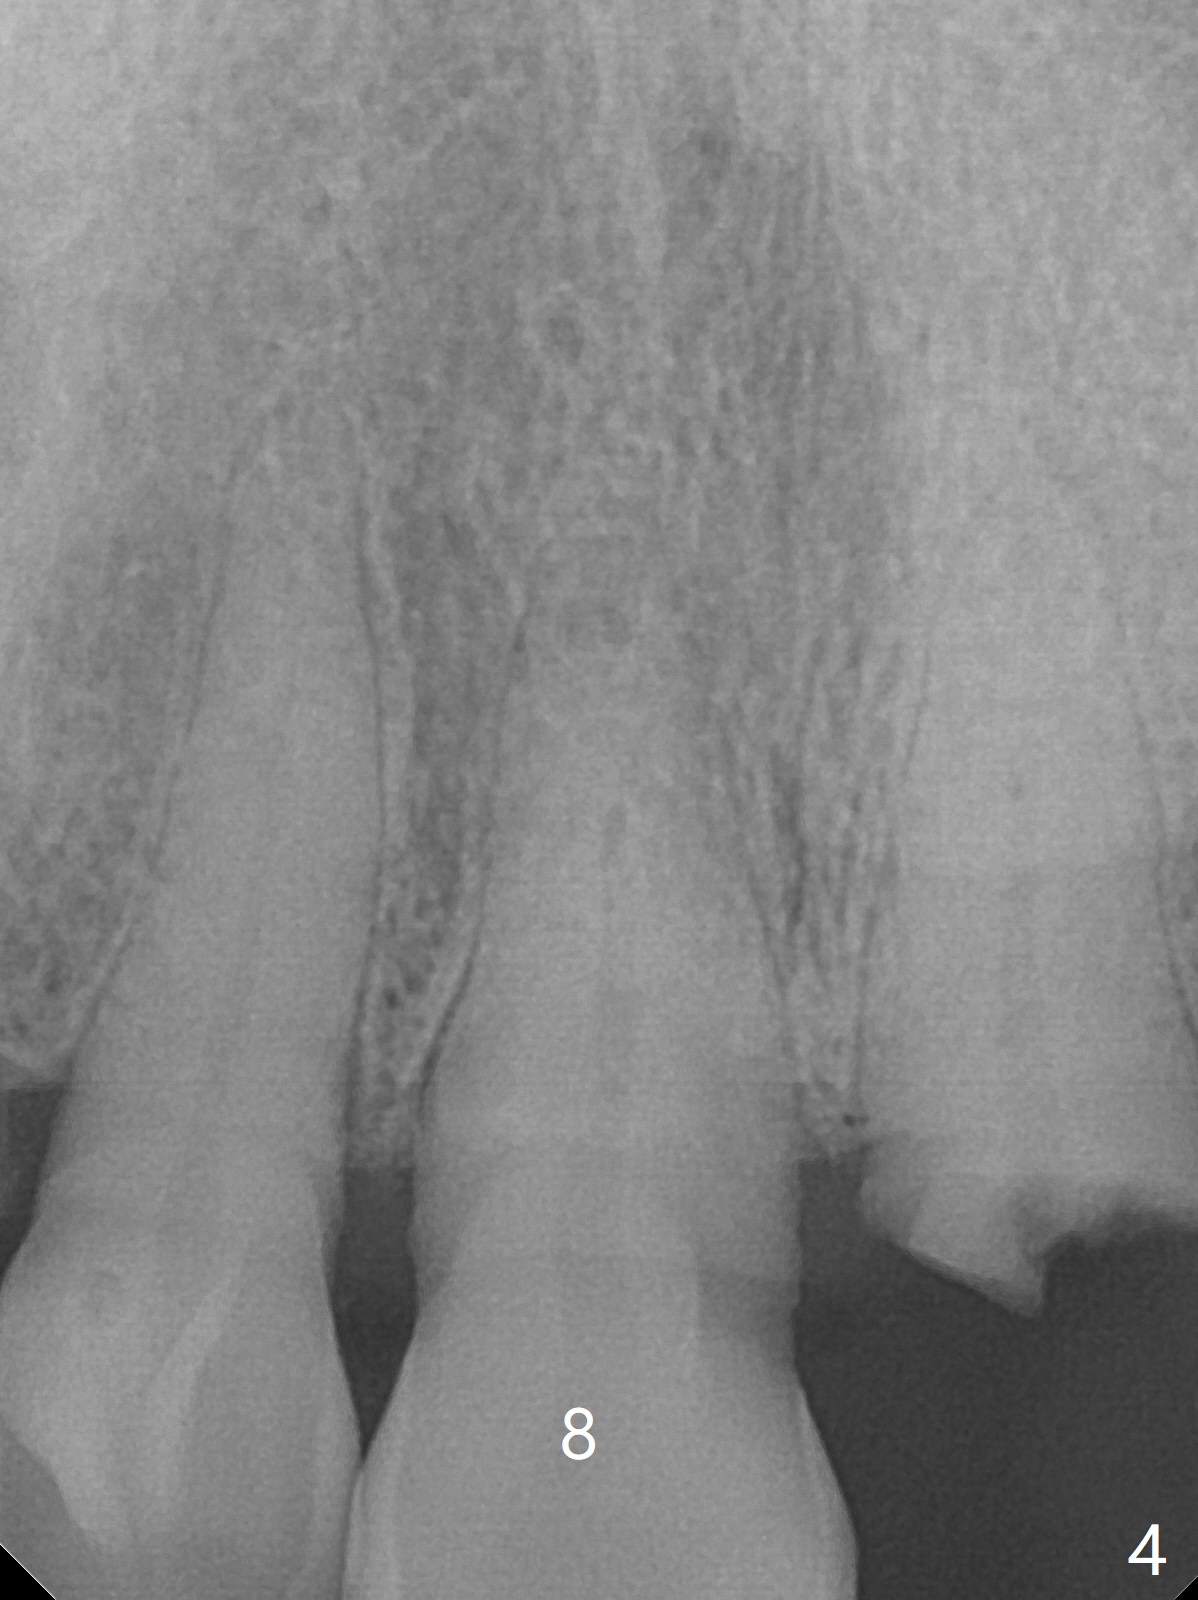

A 86-year-old woman with diabetes (under control with Insulin) and poor dentition (Fig.1) presented to clinic with an abscess apical to the tooth #8 (nonvital, Fig.2). CBCT (Fig.3) or PA (Fig.4) does not show radiolucency at #7 or 8. The incised abscess with purulent drained is superficial to the apparently intact periosteum (Fig.5 *). The patient is reluctant to have #7 and 8 extracted, since they are the only remaining functional dentition. The infection recurs 1.5 months later (Fig.6 * (^: previous incision)). With the periosteum elevated, fenetration over the apex of the tooth #7 (vital in pulpal test) is only seemingly significant finding (Fig.7). The abscess (Fig.8 A) is shown superficial to the periosteum (*). The infection is expected to relapse. What should be done otherwise? Full mouth extraction has been discussed.